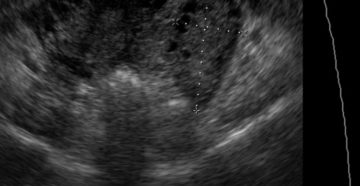

Кальцинаты в матке: причины образования, диагностика, лечение Матка является непарным полым органом, который состоит из…